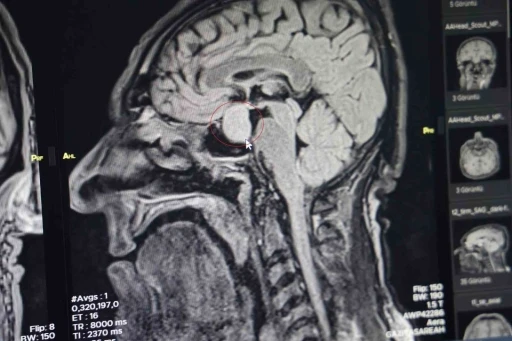

Haberler gorme kaybi gorme kaybi Haberleri Gaziantep Büyükşehir’den Doğu ve Güneydoğu Anadolu’ya hizmet edecek merkez Nöroloji uzmanından inmeye karşı uyarı: "Erken müdahale felci önler" Dünya İnme Günü’nde uzmanından uyarı: "İnme, kalıcı sakatlığa yol açan hastalıklar arasında birinci, ölüme neden olan hastalıklar arasında ise üçüncü sırada yer almaktadır" Gözleri görmüyor ama kalbiyle görüyor, sesliyle büyülüyor Her 4 dakikada 1 kişi inme geçiriyor Prof. Dr. Celkan: "Şah damarı darlığı felç ihtimalini arttırıyor" Prematüre bebeklerde görme riskine dikkat Uzmanı uyardı: "Göz sağlığı düzenli olarak kontrol edilmelidir" OP. DR. GÖKMENGİL: "ŞAH DAMARI HASTALIKLARI FELÇ RİSKİNİ ARTIRIYOR" Uzmanından uyarı: "Şah damarı tıkanıklığı felce yol açabiliyor" Görme engelli eğitmenleriyle hayata daha sıkı tutunuyorlar Darp edilen adam o anları anlattı Su kuyusu kavgasında 2 kardeş tutuklandı Kafası taşla ezilmek istenen baygın kocasını saldırganlara taş atarak kurtardı Diyabetin kontrol altında tutulması göz sağlığı için önemli Nöroloji Uzmanı Prof. Dr. Demir: "MS, genç erişkinleri en çok da 3-4 kat daha fazla olmak üzere kadınları etkileyen bir hastalık" Retina ve vitreus hastalıklarına dikkat Kruvaziyer yolcusu görme kaybı yaşadı Denize dalarken dikkat: Boyun travması ve felç riski uyarısı "Retina hastalıklarında vitrektomi cerrahisi görmeyi yeniden kazandırabilir" Dolandırıcı Kurbanı Yaşlı Adamın Kaderi Değişti! 12›»